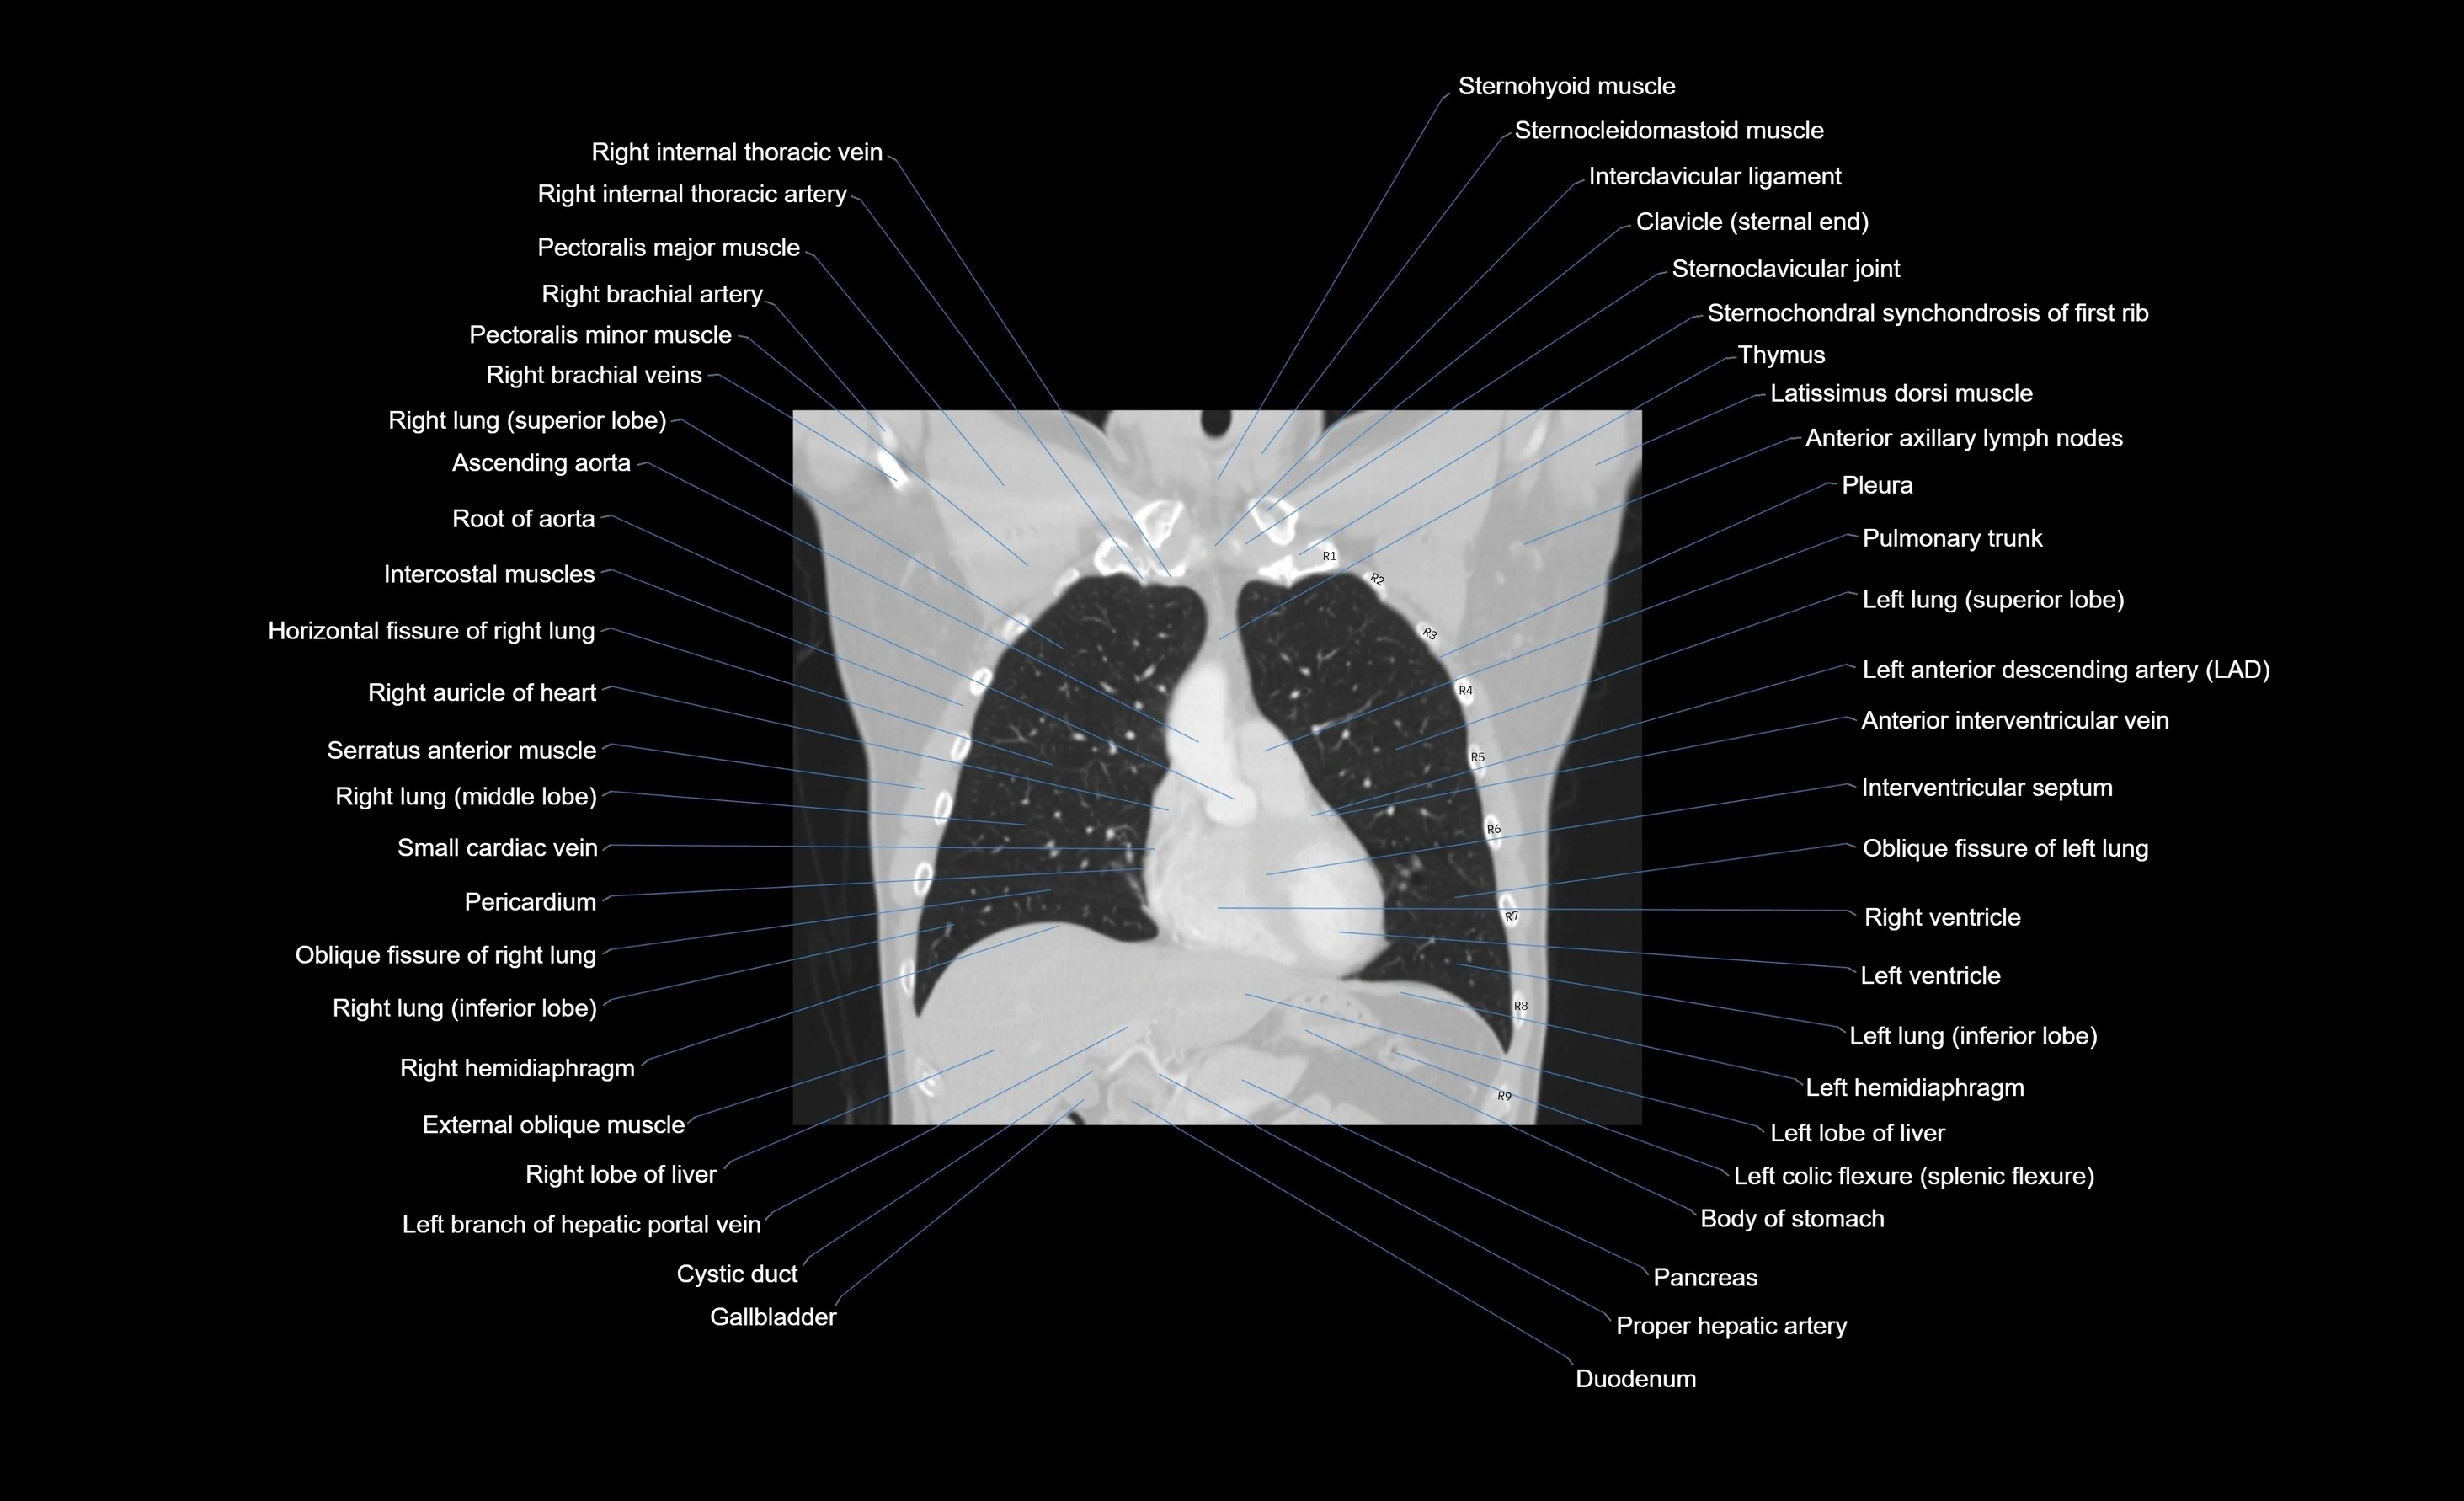

MRI images

CT images